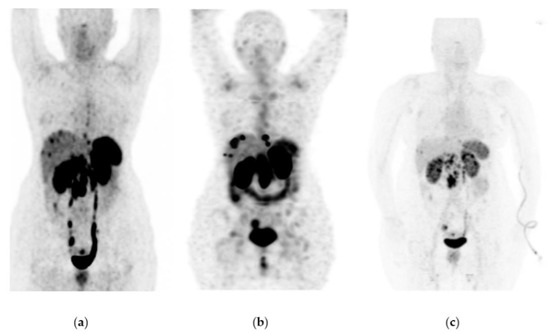

Figure 8. A 76-year-old female patient received four doses of 177Lu-DOTATOC with stable disease as determined by 68Ga-DOTATOC PET/CT imaging. Findings: 11% overall increase in somatostatin receptor expression in the primary pancreatic tumor lesion, as well as metastatic deposits in lymph nodes, liver, and peritoneal implants toward the root of the mesentery, jejunum, and pelvic cavity, without significant morphologic changes. Data refer to a stable disease. (a) 68Ga-DOTATOC PET/CT imaging before 177Lu-DOTATOC therapy, (b) 177Lu-DOTATOC SPECT imaging (first dose), (c) 68Ga-DOTATOC PET/CT imaging ten months after the first dose of 177Lu-DOTATOC.

Figure 6, Figure 7 and Figure 8 show typical clinical cases of partial response and stable disease after 177Lu-DOTATOC therapy (the stable disease does not meet the criteria for partial response or progressive disease).